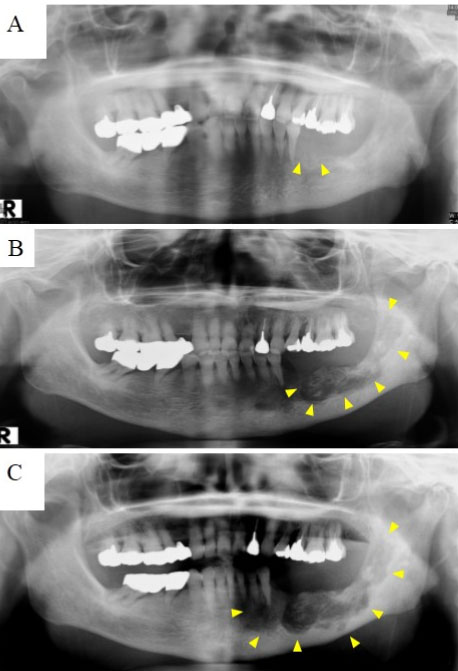

Case Report: A 42-year-old healthy man without underlying diseases or any teeth troubles suffered from severe pain in the gingival of the right mandibular bone for three weeks. The intraoral inspection revealed a well-defined elastic hard mass with a size less than 10 mm on the medial side of the right mandibular gingiva. The histopathological examination proved that the bacterial druse with radial structure invaded the bone margin widely and proliferated in some places of the bone. After removing the mass and scraping off the around bone, followed by two month-oral use of Amoxicillin (AMPC:1500 mg/day), his complaints and the gingival tissue have been entirely resolved.

Conclusion: The morphological features of the growth of actinomyces in the bone margin by the limited lesion of actinomycosis at the gingiva have not ever been reported. Even localized actinomycosis at gingiva should be adequately treated.